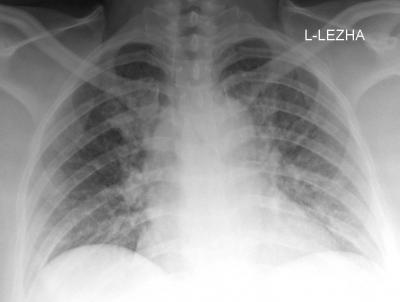

Вчера на дежурстве описывал снимочки сделаные палатным аппаратом на месте, в кардио-реанимации, пациентка 51 года, поступила в ОКБ в экстренном порядке с предворительныи диагнозом: ИБС. Острый коронарный синдром. Вданном случае имеет место быть случайной находке, дальше конечно больше, но пока предоставлю снимок обзорный органов грудной клетки, для размышления:

Справа на уровне 3 мребра визуализируется теневой синдром "круглая тень".

И, как всегда, без бокового снимка, судить о субстрате данного скиалогического образования не представляется возможным, ибо может быть все, что угодно, вплоть до образования на коже.

Всё верно, уважаемый Валентин Львович, фокусное затемнение малой интенсивности, при этом смотриться с ровными и чёткими контурами. Могу гарантировать вам, что это не образование на коже.

С учетом величины образования и его весьма малой интенсивности тени, почти "нежной" тени, с довольно ровными, но нечеткими контурами, рискну предположить, что данная тень, скорее, имеет принадлежной к плевре - к костальной или интерлобарной, но это всего лишь предположение, ибо Вы сами прекрасно понимаете, что без правой боковой рентгенограммы, любой рентгенолог не отважится сделать даже приблизительное предположение о патологическом процессе или патологическом состоянии.